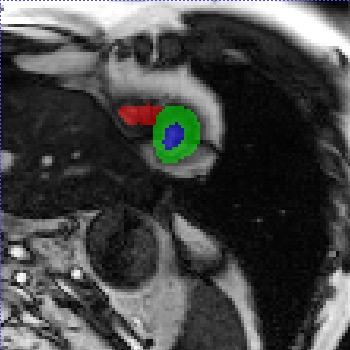

Transformers, the default model of choices in natural language processing, have drawn scant attention from the medical imaging community. Given the ability to exploit long-term dependencies, transformers are promising to help atypical convolutional neural networks (convnets) to overcome its inherent shortcomings of spatial inductive bias. However, most of recently proposed transformer-based segmentation approaches simply treated transformers as assisted modules to help encode global context into convolutional representations without investigating how to optimally combine self-attention (i.e., the core of transformers) with convolution. To address this issue, in this paper, we introduce nnFormer (i.e., Not-aNother transFormer), a powerful segmentation model with an interleaved architecture based on empirical combination of self-attention and convolution. In practice, nnFormer learns volumetric representations from 3D local volumes. Compared to the naive voxel-level self-attention implementation, such volume-based operations help to reduce the computational complexity by approximate 98% and 99.5% on Synapse and ACDC datasets, respectively. In comparison to prior-art network configurations, nnFormer achieves tremendous improvements over previous transformer-based methods on two commonly used datasets Synapse and ACDC. For instance, nnFormer outperforms Swin-UNet by over 7 percents on Synapse. Even when compared to nnUNet, currently the best performing fully-convolutional medical segmentation network, nnFormer still provides slightly better performance on Synapse and ACDC.